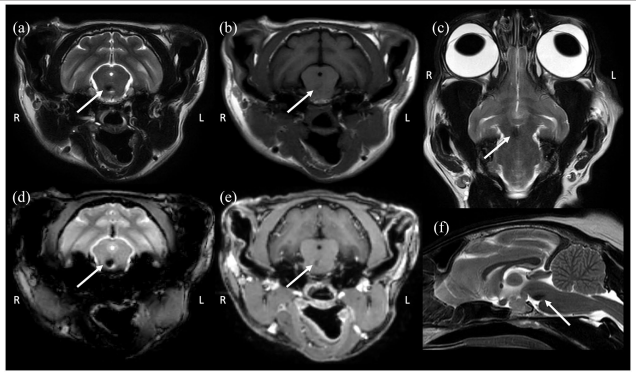

전신고혈압과 관련이 있는 것으로 추정되는 가역성의 안면신경 마비가 있는 고양이 증례

전신고혈압으로 인하여 발생한 뇌출혈등으로 안면신경 마비가 올 수도 있다는 의미이지

안면신경이 마비된 상태는 전신고혈압을 의미한다고 여기면 안됨

안면신경 마비가 있는경우 뇌 MRi 를 반드시 촬영해 보라는 논문으로 해석하는 편이 옳음 (다른 증례는 종양이었음)